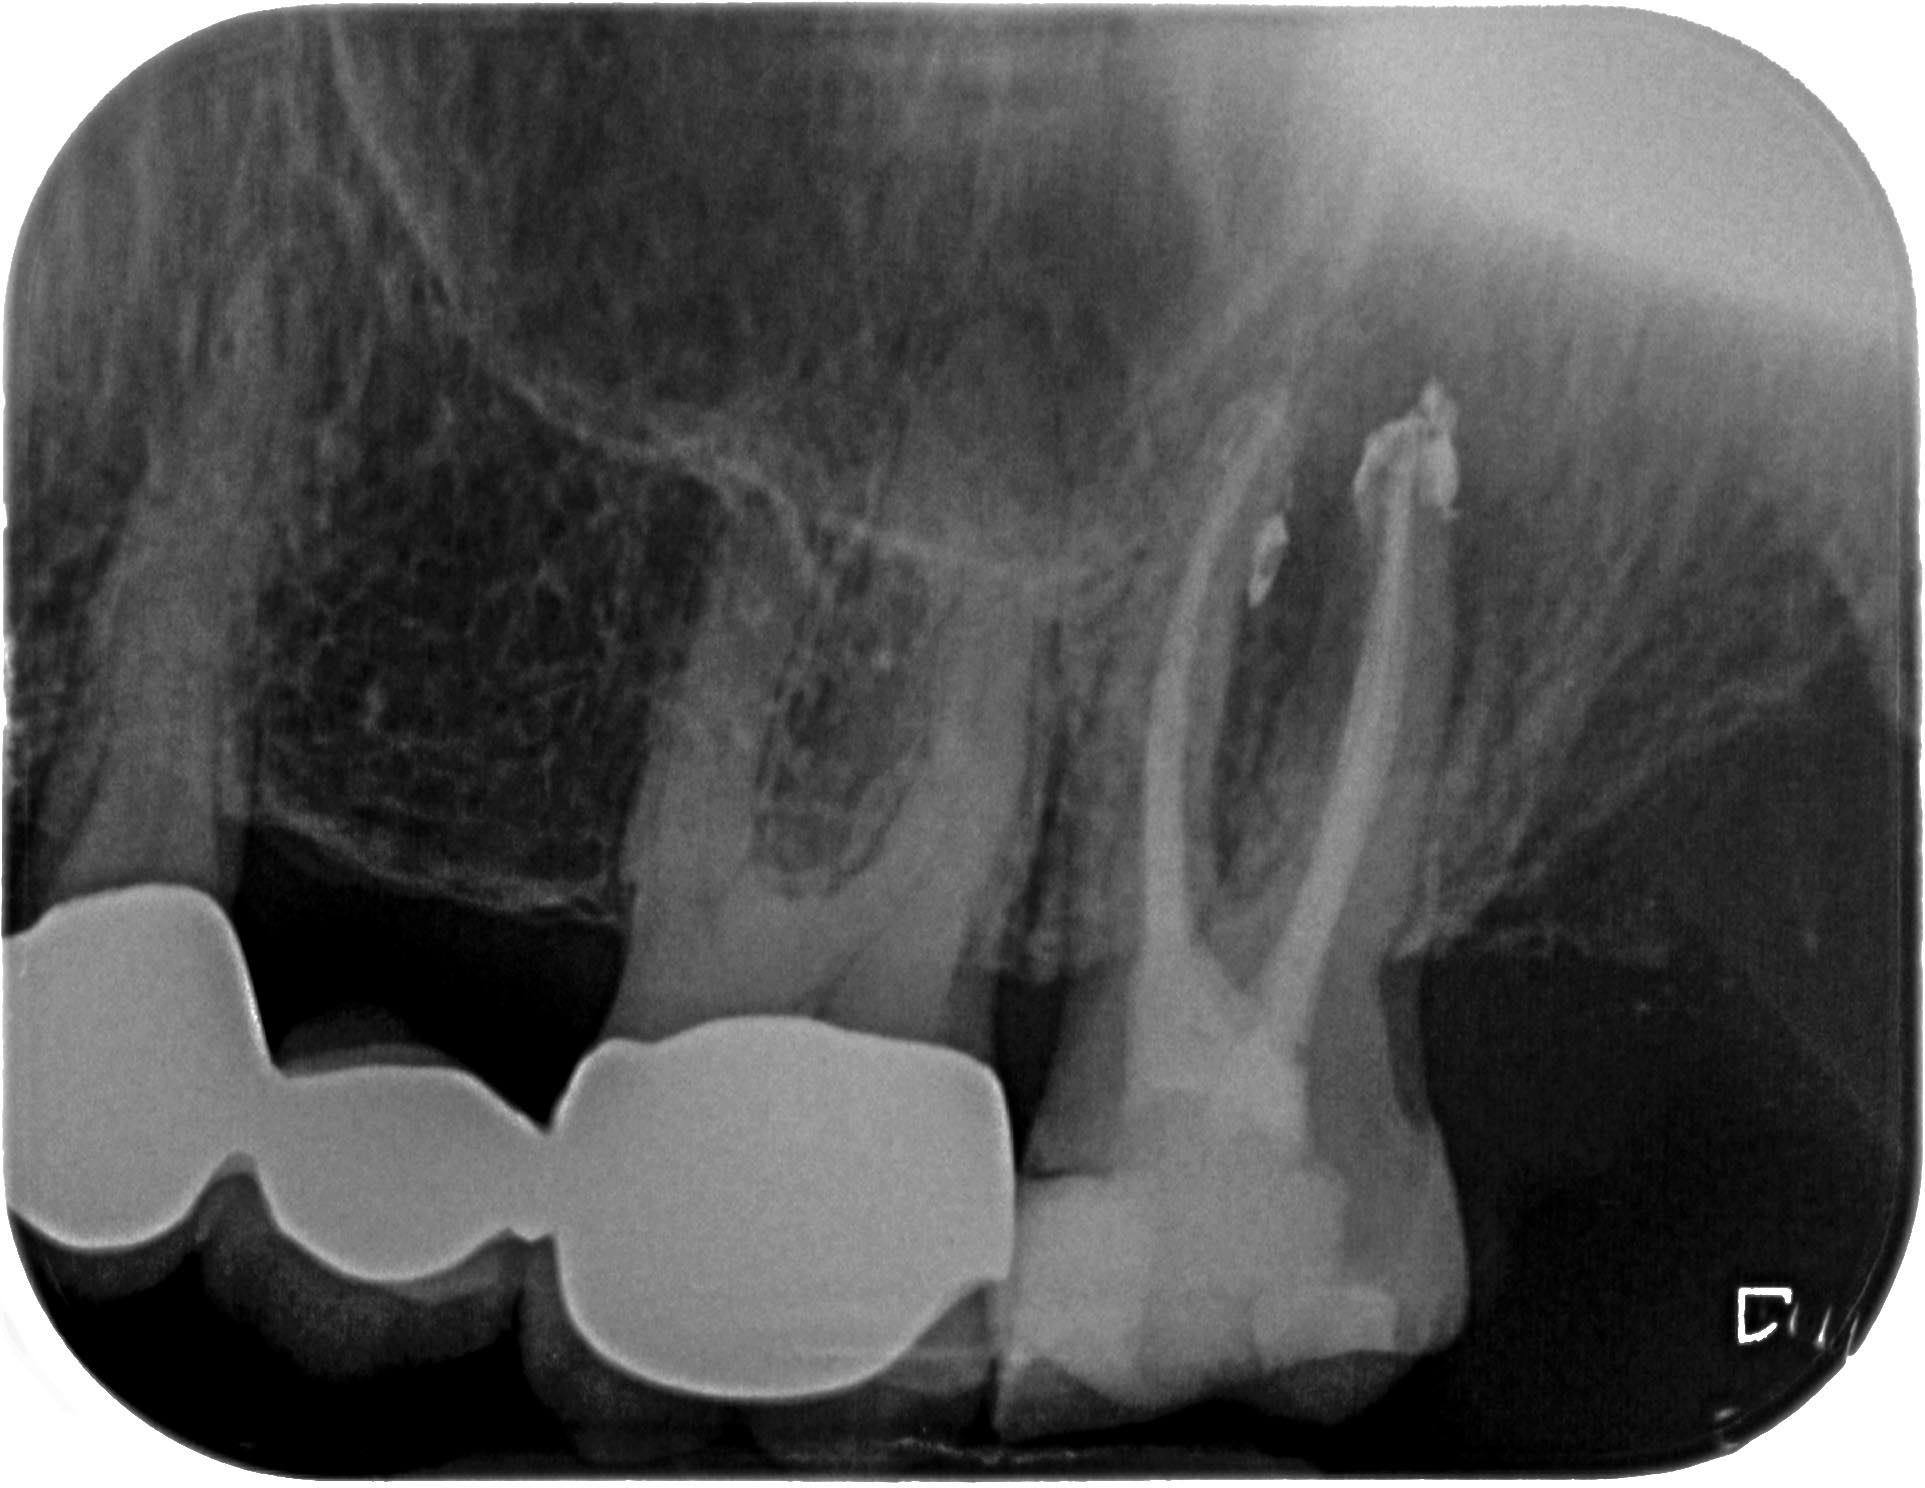

SE_27-3 Veröffentlicht 4. Mai 2014 am 1925 × 1488 in Massive apikale Aufhellung an Zahn 27 im Recall WF – Kontrolle orthograd